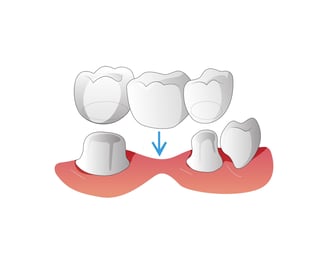

Los puentes reemplazan uno o más dientes faltantes mediante la unión de una prótesis entre dos coronas colocadas sobre dientes naturales o implantes adyacentes.

Puentes Dentales